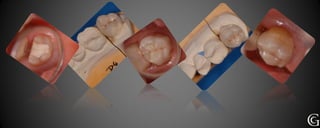

Restauraciones Plásticas

Las restauraciones plásticas, son realizadas con un material de base orgánica

y refuerzo cerámico, conocido como composite. Polimeriza (endurece)

cuando se lo expone a la luz halógena. El composite se moldea en boca, es

por esto que se llaman restauraciones directas.

Buscando estética, imitando lo natural

Restauraciones Plásticas Las restauracionesplásticas, son realizadas con un material de base orgánica y refuerzo cerámico, conocido como composite. Polimeriza (endurece) cuando se lo expone a la luz halógena. El composite se moldea en boca, es por esto que se llaman restauraciones directas.

Prótesis Fija Convencional Restauracionesparciales “incrustaciones” Las incrustaciones son restauraciones que involucran parte de la pieza dentaria, confeccionadas fuera de la boca (indirectas parciales) que luego son adheridas al diente en tratamiento. Pueden ser de diversos materiales, cerámicas, composite o metálicas.

Manteniendo una buena comunicacióncon el laboratorio dental, se logra mimetizar la restauración con el remanente dentario Técn. J.C. Sebático